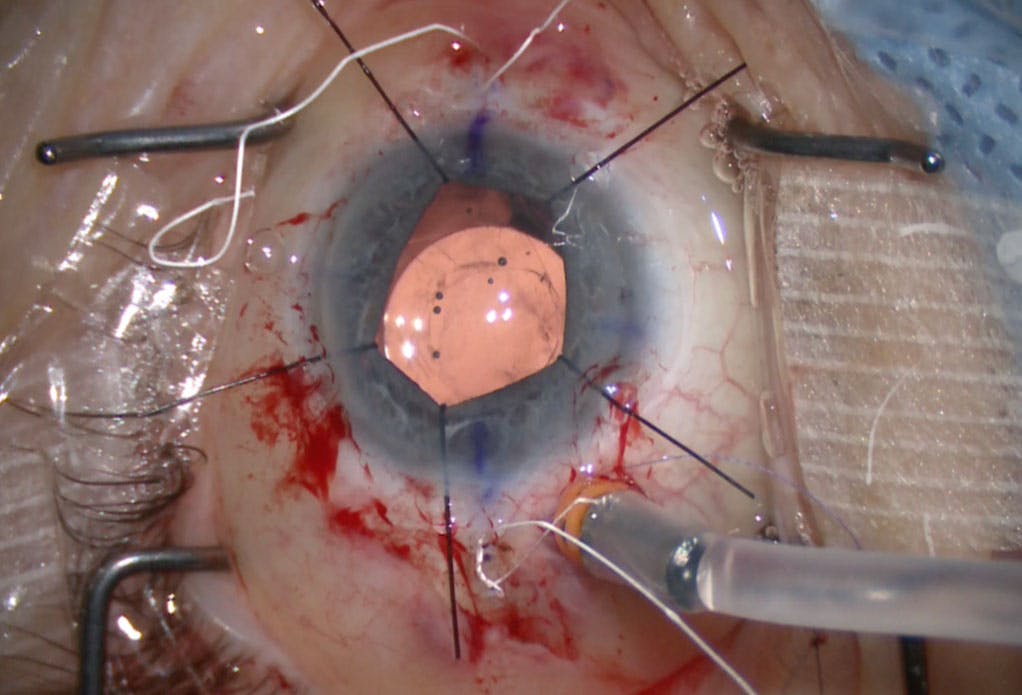

In the case presented earlier, an initial attempt was made to reposition the IOL using the lasso technique while preserving the capsular bag. During manipulation, tension split the capsular bag, causing the suture to slip along the haptic (a common occurrence in DBS) and confirming the bag’s nonviability (Figure 3). At that point, the decision was made to remove the entire capsular bag–IOL complex and proceed with secondary IOL placement via scleral suture fixation.

Figure 3. An intraoperative photograph demonstrated failure of the capsular bag during attempted IOL repositioning via a lasso technique and confirmed nonviability of the capsule to hold fixation.

In our practice, we have learned from cases such as this one to resist the temptation to reposition a dead bag. Early recognition and decisive IOL removal can reduce operative morbidity.